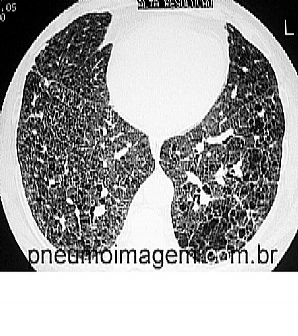

Veja imagens de Fibrose Pulmonar Idiopática no PneumoImagem, clique aqui.